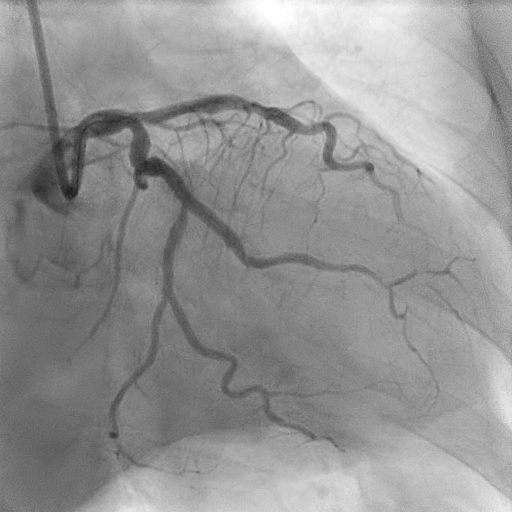

Relevant Catheterization Findings

Coronary angiogram showed two vessel disease with severe stenosis at the obtuse marginal (OM), distal left circumflex (LCx) artery and distal right coronary artery (RCA) with mild disease at the proximal left anterior descending artery (LAD).